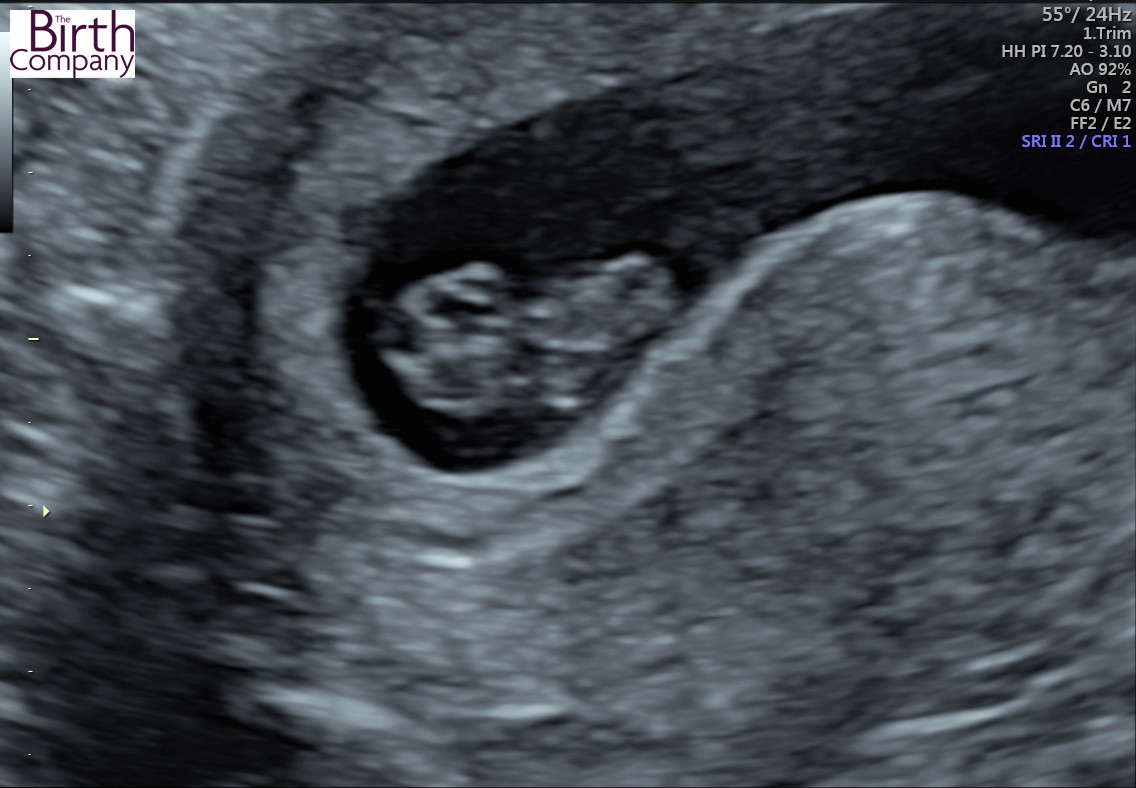

8 week ultrasound, can anyone help?

Apologies as I did not read about this until after I had my ultrasound so I did not ask which side the placenta is and now i can't figure it out myself!

Fetus is 8 weeks 3 days and the yolk sac was to the left of it.

Can anyone tell if boy or girl or maybe a more educated guess than me? :flowerz::flowerz::flowerz: